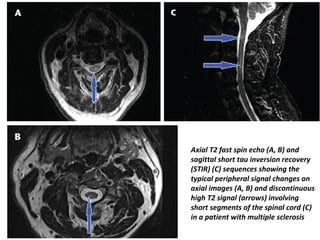

Axial T2 fast spin echo (A, B) and

sagittal short tau inversion recovery

(STIR) (C) sequences showing the

typical peripheral signal changes on

axial images (A, B) and discontinuous

high T2 signal (arrows) involving

short segments of the spinal cord (C)

in a patient with multiple sclerosis

Axial T2 fastspin echo (A, B) and sagittal short tau inversion recovery (STIR) (C) sequences showing the typical peripheral signal changes on axial images (A, B) and discontinuous high T2 signal (arrows) involving short segments of the spinal cord (C) in a patient with multiple sclerosis